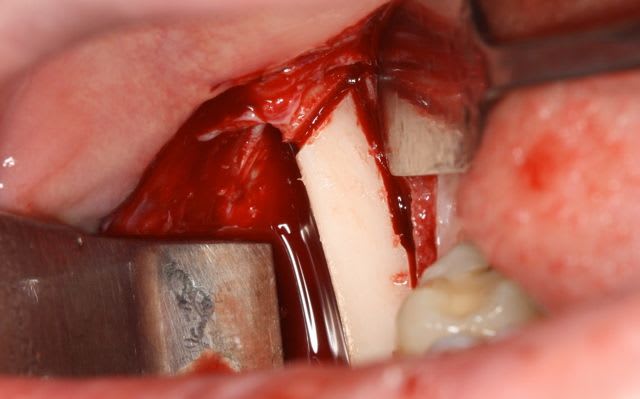

dépose des vis et pose de l'implant à 5mois1/2 avec un cj roulé et mise en place de la vis de cica,

pour la greffe: un lit de copeaux généreux et un bloc corticale par dessus et des copeaux pour boucher les espaces. Pas de membrane par dessus, seulement le périoste.

tu n'as pas mis de membrane:

Je me souviens d'un cours du Prof. Zöller à Cologne, qui ne recommande pas les membranes, car ça gênerait l'alimentation sanguine du greffon à partir du perioste.